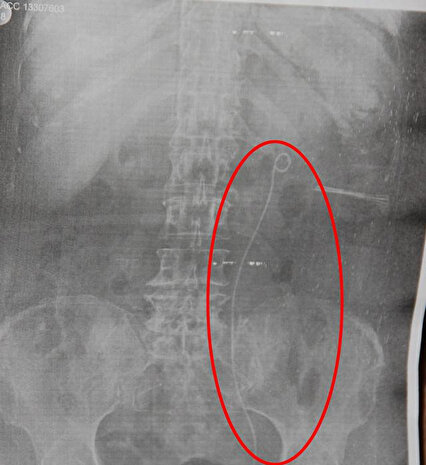

Operasyonu başarısızlıkla sonuçlanan Yıldız Sessiz Aslım, böbreğinde sadece düşürülemeyen taş olduğunu zannederken her şeyden habersiz böbreğinde unutulan kateter teli ile evine geri döndü. Bir süre sonra yüzünde şişlik, yüksek ateş ve iştahsızlık sebebiyle aynı hastaneye yeniden başvuran Aslım’a böbreğinin enfeksiyon kaptığı belirtildi ancak yapılan tetkiklerde tel unutulduğu anlaşılmadı.

Tam 5 yıl böbreğinde telle yaşayan talihsiz kadın, yaşadığı çeşitli şikayetlerin böbrek taşı sebebiyle olduğunu zannetti. Geçen mayıs ayında idrarında yoğun kanama fark eden Yıldız Sessiz Aslım, bu kez Tepecik Eğitim ve Araştırma Hastanesi'ne başvurdu, yapılan tetkiklerde böbrekte metal teller fark edildi. Kasım ayında operasyona alınan Yıldız Sessiz Aslım, böbreğindeki telden kurtulsa da organ yüzde 80 oranında hasar gördü. Aslım, konuyla ilgili dava açacağını belirtti.

- Kanser tedavisi sonrası başına gelen olayı atlatamadığını belirten Yıldız Sessiz Aslım, "2013 yılında böbrek rahatsızlığı nedeniyle hastaneye başvurdum. Hastanede böbreğimde taş olduğunu söylediler. Taşı çıkaramayınca kateter yardımı ile taşı düşürmeye çalışacaklarını belirttiler. 20 gün hastanede yattım. Taş yine düşmedi. Ben hastaneden çıktım ama meğer kateter çıkarılırken teli böbreğimde kalmış. Bir süre şikayetlerim oldu. Yüzüm şişiyordu, ateşlenme vardı, iştahsızdım. Hastaneye gittiğimde bana 'Böbreğin enfeksiyon kapmış' dediler. Kateter teli kaldığı için enfeksiyon olmuş ama gerçeği 5 yıl sonra başka bir hastanede öğrendim. Böbreğimde kateter teli unutulduğu için 5 yıl bu telle yaşamışım. Böbreğim şu anda yüzde 21 oranında çalışıyor. Beni sağlığımdan ettiler. Benim böbreğimi geri getirecekler mi?" diye sordu.

5 yıl boyunca yaşadığı şikayetleri hep böbreğindeki taşa bağlayan Yıldız Sessiz Aslım, geçen mayıs ayında idrarından yoğun kan gelince durumdan iyice şüphelendiğini ve başka bir hastaneye başvurduğunu söyledi. Yıldız Sessiz Aslım, "Orada böbreğimde metal teller olduğu tespit edildi. Ben o sırada böbreğimde tel unutulduğunu bilmediğim için şaşırdım, merak ettim. Tetkiklerden sonra kateter teli unutulduğu anlaşıldı. Ben şifa bulmak için gittim, beni dert sahibi ettiler" diye konuştu.

Yaşadığı olayı "skandal" olarak nitelendiren Aslım, sözlerini şöyle sürdürdü: "Bunu nasıl böbreğimde bıraktılar bilmiyorum. Diğer hastanedeki doktorlar böbreğimde kateter teli unutulduğunu söylediğinde şoke oldum. Unutulan tel 1 santim değil, 2 santim değil. Neredeyse 50 santim. İnsan miyop olsa yine görür. Ben dava açacağım. Hakkımı soruna kadar arayacağım. Bu olay yüzünden sağlığımı kaybettim."